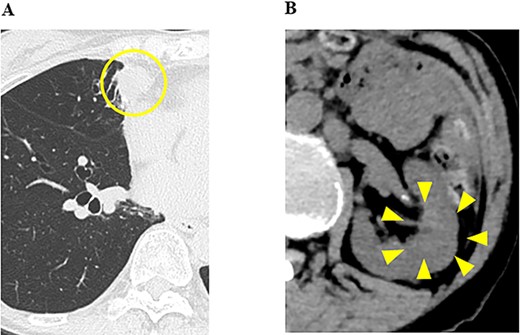

A79-year-old female underwent right thyroid lobe resection and cervical lymph node dissection for PTC at a previous hospital. Five years after the initial surgery, follow-up computed tomography (CT) revealed multiple masses in both lung fields, with the largest tumors in the middle lobe of the right lung measuring 2.6 cm. These tumors previously showed a high signal intensity in the early phase of contrast-enhanced CT (Fig. 1A-1). A mass of ~4 cm was detected in the left kidney with a tumor plug in the left renal vein (Fig. 1A-2). From the CT findings and clinical course, primary renal cell carcinoma (RCC) with multiple pulmonary metastases were strongly suspected, and the administration of nivolumab and ipilimumab was initiated. Five months later, CT showed increases in the sizes of the pulmonary tumors (Fig. 1B-1) and a decrease in the size of the renal tumor (Fig. 1B-2).

CT images of the chest and abdomen; (A) at the start of the administration of nivolumab and ipilimumab, CT showed multiple masses in both lung fields and a mass in the left kidney with a tumor plug in the left renal vein, and (B) 5 months after the administration of nivolumab and ipilimumab, CT showed increases in the sizes of the pulmonary tumors and a decrease in the size of the renal tumor, and (C) 6 months after the administration of nivolumab and ipilimumab, CT showed increases in the sizes of the pulmonary tumors and pleural effusion (yellow arrows).